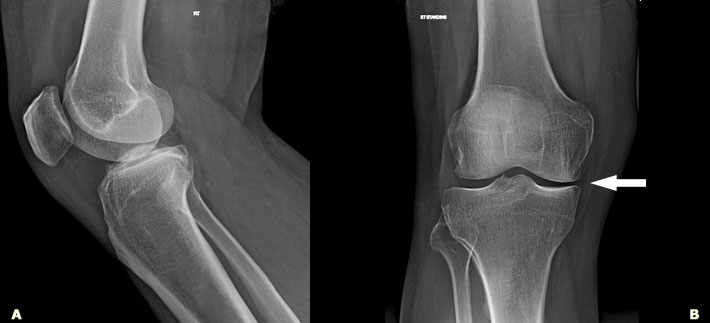

骨头疾病的发生率,特别是高龄加上肥胖率上升与缺乏身体活动的族群,一直在稳性增加;如此之多,以至于被认为在未来的几年内,会增加一倍。

到目前为止,骨骼移植是这个问题唯一的解决之道。但来自加州大学圣地牙哥分校(University of California in San Diego)的研究人员,现在已经发现一个更为快速而有效率的方法,来再生骨头组织。这是再生医学的一项重大进展,特别是对于工程骨头组织;然后能够被使用到有严重骨头缺陷的病患,或是遭受到令人痛苦的骨头伤害。

研究人员这项发现的关键在于腺甘酸的使用。这个自然生成的分子能够被注射到骨头组织,来诱发人类多功能干细胞(多功能干细胞有能力形成身体内任何类型的细胞)的再生。在实验中,这个方法协助修复老鼠头盖骨的缺陷,而没有引起传染或肿瘤。